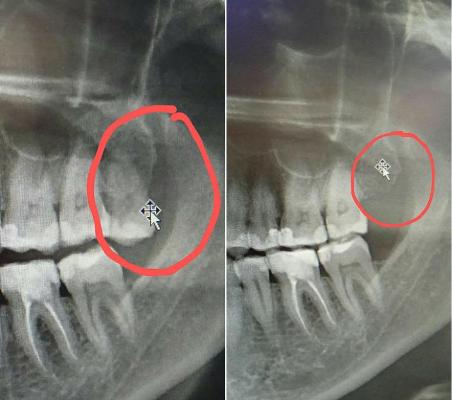

Пациентка Г.Л. обратилась в клинику №1 ВиТерра Беляево к врачу-стоматологу Халяпину А.В. с жалобами на ноющие боли в области верхней челюсти слева.

При осмотре зуб 2.8 выявлена кариозная полость на жевательной поверхности.

Зуб расположен вне зубного ряда. Качественно вылечить зуб не представляется возможным. Принято решение об удалении проблемного зуба.